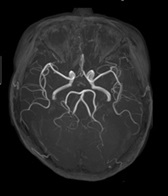

非造影頭部MRA

CTにおいては、血管描出のためには、造影剤を必ず用います。しかし、MRIは造影剤がなくても頭部や腹部、下肢全体などの血管を描出することができます。コントラストも良く明瞭で、何より安全に検査ができます。